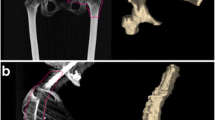

Aide N, Talbot M, Fruchart C et al (2018) Diagnostic and prognostic value of baseline FDG PET/CT skeletal textural features in diffuse large B cell lymphoma. Eur J Nucl Med Mol Imaging 45(5):699–711. https://doi.org/10.1007/s00259-017-3899-6

Mayerhoefer ME, Riedl CC, Kumar A et al (2020) [18F] FDG-PET/CT radiomics for prediction of bone marrow involvement in mantle cell lymphoma: a retrospective study in 97 patients. Cancers (Basel) 12(5):1138. https://doi.org/10.3390/cancers12051138

Kenawy MA, Khalil MM, Abdelgawad MH et al (2020) Correlation of texture feature analysis with bone marrow infiltration in initial staging of patients with lymphoma using 18 F-fluorodeoxyglucose positron emission tomography combined with computed tomography. Pol J Radiol 19(85):e586–e594. https://doi.org/10.5114/pjr.2020.99833